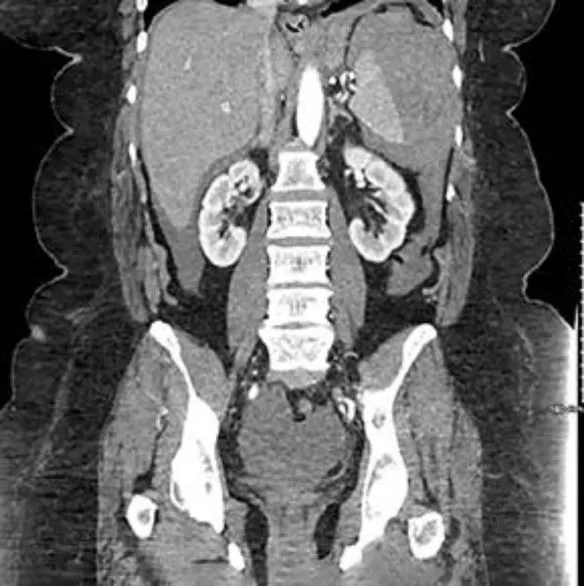

При поступлении в стационар у пациентки отмечена гипотония — АД 73/38 мм рт. ст., ЧСС 75 ударов в минуту, уровень гемоглобина составлял 101 г/л. При РКТ органов брюшной полости выявлена гематома в области селезенки размером до 4 см (рис. 1). Поскольку экстравазация отсутствовала, было принято решение о консервативной терапии. В ходе лечения отмечалось снижение уровня гемоглобина до 73 г/л, что потребовало гемотрансфузии. Через 7 суток пациентка была выписана из стационара.

image001.jpg

Рисунок 1 [1].